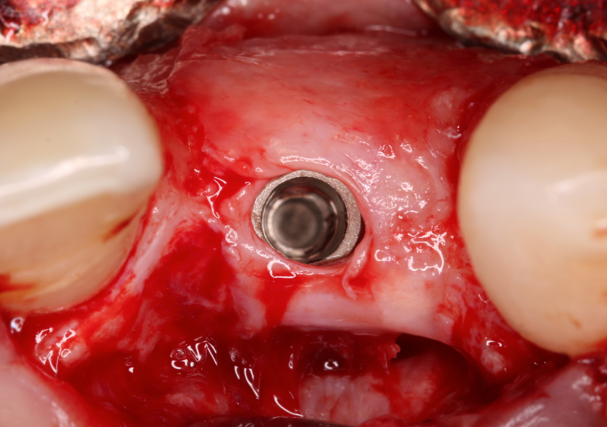

Foi estabelecido tratamento regenerativo prévio (Urban, 2013) (Fig.2/3) com membrana de PTFE-d (Cytoplast TXT250 Vestibular 17mm x 25mm) e posterior instalação de implante do tipo cone morse (Due Cone – Implacil De Bortoli) e tapa implante (Max Cover – 2mm), obedecendo todos os critérios de filosofia de tratamento para tal (Nentwig, 1987). Fig.4A/B

Fig. 3